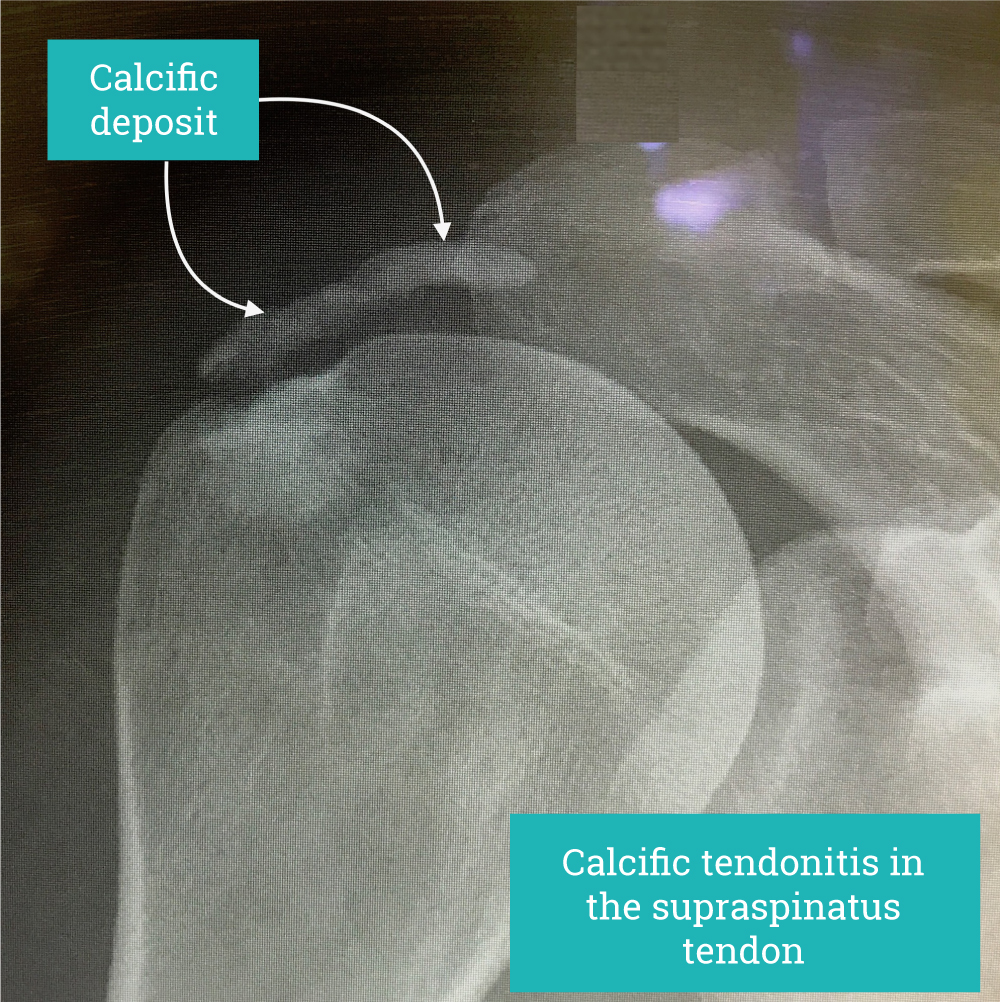

Calcific Tendonitis

This is often asymptomatic and is often seen as an incidental finding on x-ray in individuals without pain.

The crystals typically form within the rotator cuff and provoke symptoms either locally in the tendon by provoking the release of inflammatory mediators; Leaking into the subacromial bursa around the tendons causing a very acute flare of inflammation or by simply increasing the thickness of the tendon leading it to rub against the acromial bone with shoulder movement resulting in impingement like symptoms.